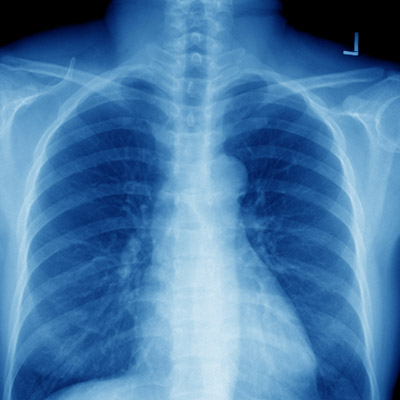

Dr Gareth Roberts is an experienced Consultant in Respiratory Medicine.

“I welcome private patients who are worried about any symptoms such as a chronic cough, wheezing or other chest problems. I can also arrange to see people quickly after they find out a chest X-ray is abnormal and that further investigations are necessary.